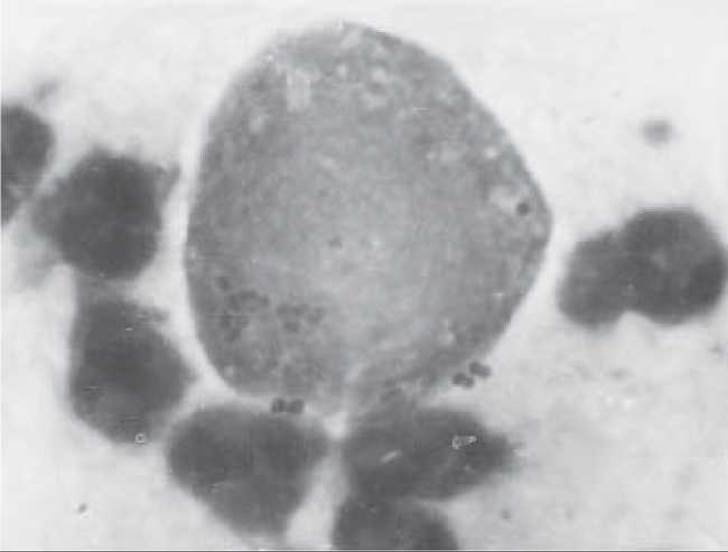

Єдиною формою, що виявляється в тканинах, є амебоподібний трофозонт (вегетативна форма організму). Розміри його складають 15-30 мкм, Цитоплазма має зернисту будову і може містити еритроцити (патогномонічна ознака), але звичайно не містить бактерій. При фарбуванні залізним гематоксиліном чи за методом Гоморі видно, що мембрана ядра паразита складається з дрібних зерен хроматину правильної форми, що утворюють добре помітну рівну мережу по периферії ядра. Ядерце розташоване в центрі ядра, має невеликі розміри і добре зафарбовується. У свіжовзятому матеріалі трофозонти рухаються звичайно швидше й в одному напрямку. Можливе тривале носійство, що відіграє певну роль в епідеміології амебіазу. Крім амебної дизентерії, цей паразит може викликати захворювання сечостатевої системи.

У регіонах, де часто зустрічаються амебні коліти, у мазках з піхви і шийки матки можуть виявлятися амеби. Іноді подібні з амебами мікроорганізми виявляють у жінок, які користуються внутрішньоматковими протизаплідними засобами. При цитологічному дослідженні мазків вегетативні форми цих мікроорганізмів (трофозонти) являють собою круглі й овальні базальні структури різного розміру (у середньому 15-20 мкм) з ексцентрично розташованим круглим ядром. Основна ознака, що дозволяє їх ідентифікувати, - наявність у цитоплазмі поглинених еритроцитів. Ці амеби дуже схожі на види, що живуть у порожнині рота.

У випадках поєднаного інфікування сечостатевих органів збудниками венеричних інфекцій і амебами характер їхньої взаємодії може впливати на розвиток, перебіг і наслідки захворювання. Зокрема, нами встановлена здатність кишкової амеби поглинати гонококи, охороняючи їх від впливу етіотропної терапії. Наступні багаторазові рецидиви гонореї пов’язані із вивільненням резервованих в амебах гонококів. Це слід враховувати при призначенні етіотропної терапії змішаної амебно-гонококової інфекції (рис. 47).

Рис. 47. Змішана амебна та гонококова інфекція. Кишкова амеба, що поглинула гонококи, х 800.